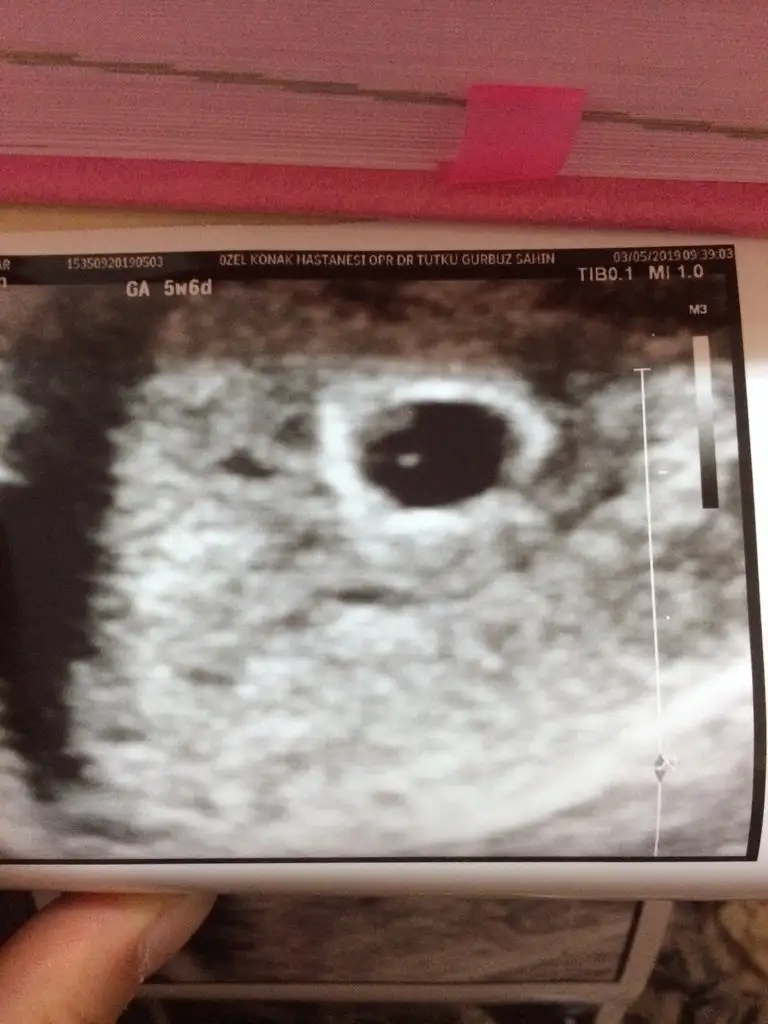

Erkege benziyor benceKizlar 8 haftalik burada yukarida da kesedeki yeri daha cok belli oluyor ne diyorsunuz tahmini olarak

Karından ise kız vajinal ise erkekKızlarrrrrrrrr merhaba sizce ??